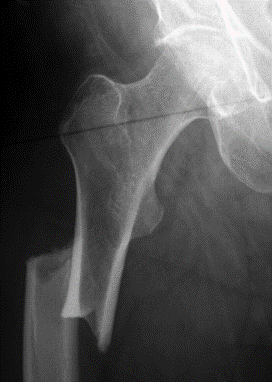

Our patient is a 65-year-old female with groin pain for three months. The pain is dull and unrelenting without an inciting traumatic event. Orthopedic tests were non-specific and an AP radiograph of the hip was performed. Figure 1 demonstrates a focal periosteal reaction with cortical thickening along the lateral cortex of the proximal femoral diaphysis. A horizontal radiolucent fracture line is visualized traversing this area of cortical thickening. This finding demonstrates an incomplete insufficiency fracture of the proximal femoral diaphysis, known as an atypical fracture of the proximal femur.

It is important to understand the radiographic findings of an early incomplete atypical proximal femoral fracture, as the radiographic findings can be extremely subtle. In some cases, the only finding is focal cortical thickening (figure 2). This fracture always starts at the lateral cortex and will progress medially. It is found distal to the subtrochanteric region within the diaphysis. The fracture is usually transverse or oblique and may have a “beaked” appearance of one cortex (figure 3).